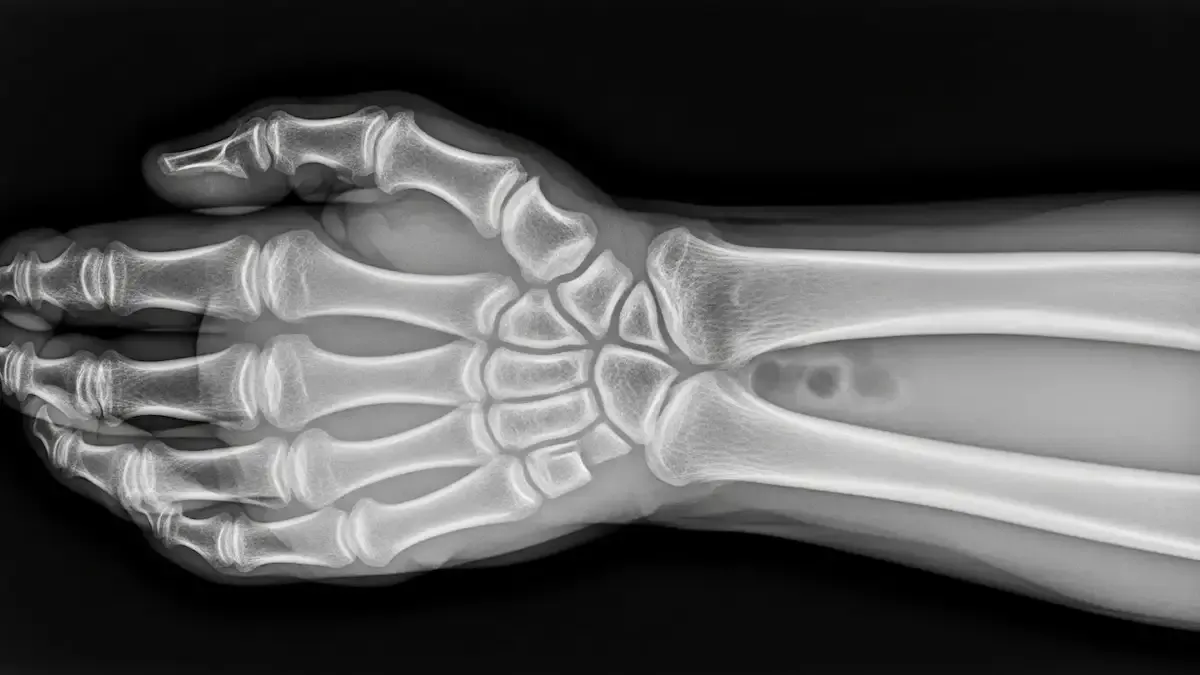

Como Saber Se Desloquei O Dedo Da Mão?

Lesões nos dedos são frequentes no consultório, principalmente após quedas, impactos ou atividades esportivas. Muitos dos meus pacientes ficam na dúvida: como saber se desloquei o dedo da mão? A luxação acontece quando os ossos da articulação saem...